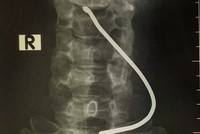

Hình ảnh chiếc thanh sắt cắm vào cổ bệnh nhân. (Ảnh: PV/Vietnam+).

Người đàn ông bị thanh sắt bắn vào cổ do nổ lốp xe ôtô tải